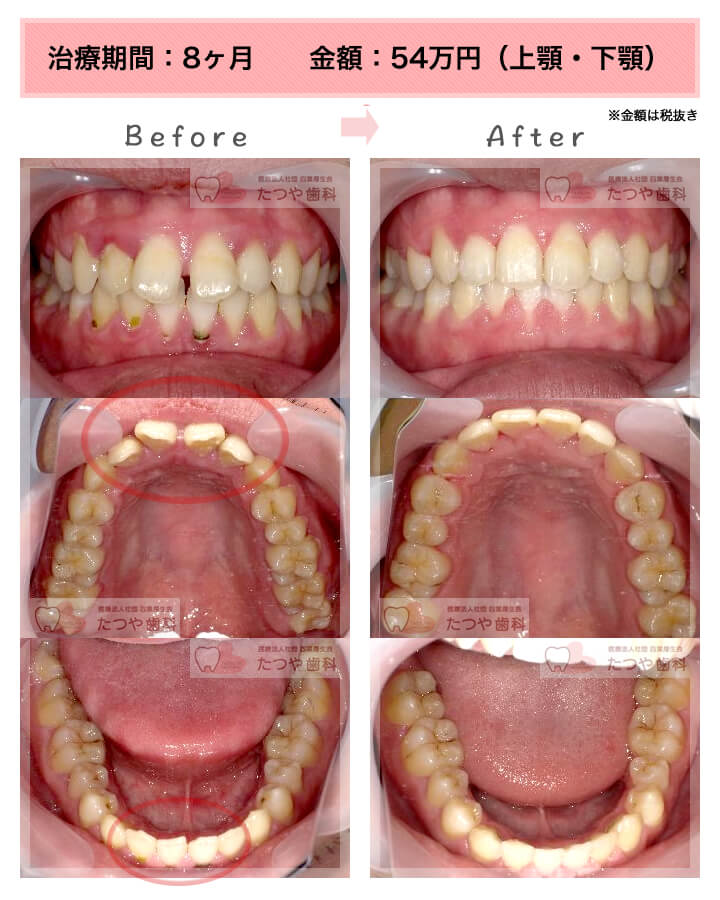

症例:上下顎の部分矯正

症例_003 前歯「すきっ歯」症例

治療期間:8ヶ月金額:48万円+税30代女性すきっ歯